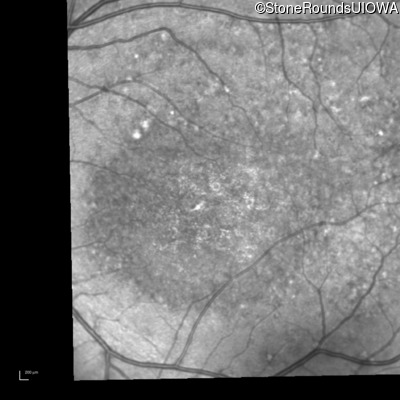

Blue Autofluorescence - Left - 10/125 -1

Exemplar